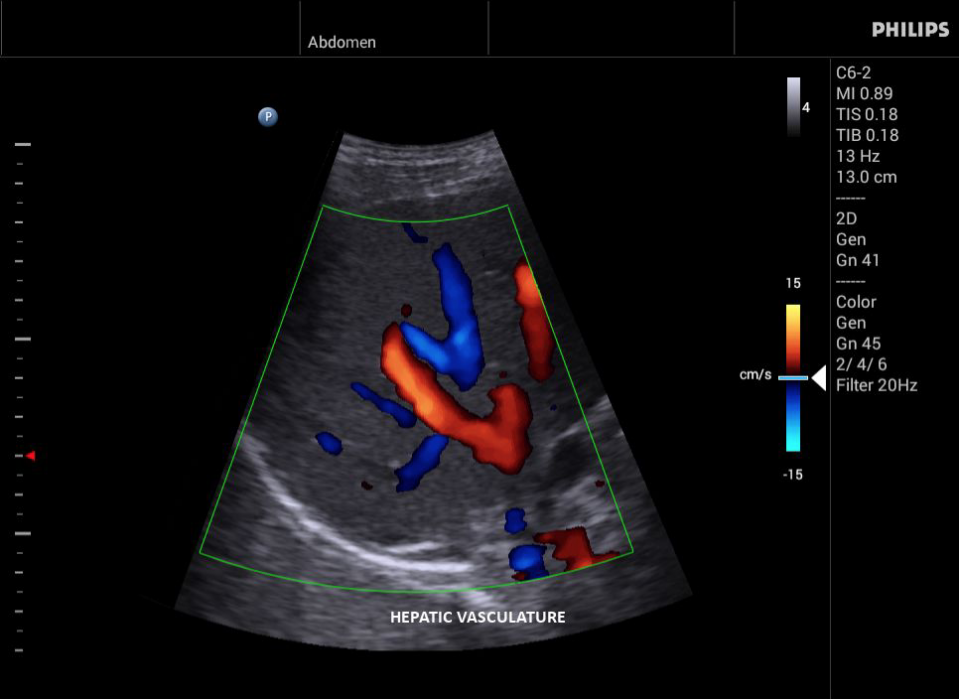

• Общие абдоминальные исследования;

• Исследования сосудов;

• Цветное допплеровское картирование

• Конвексный УЗИ датчик Philips С6-2